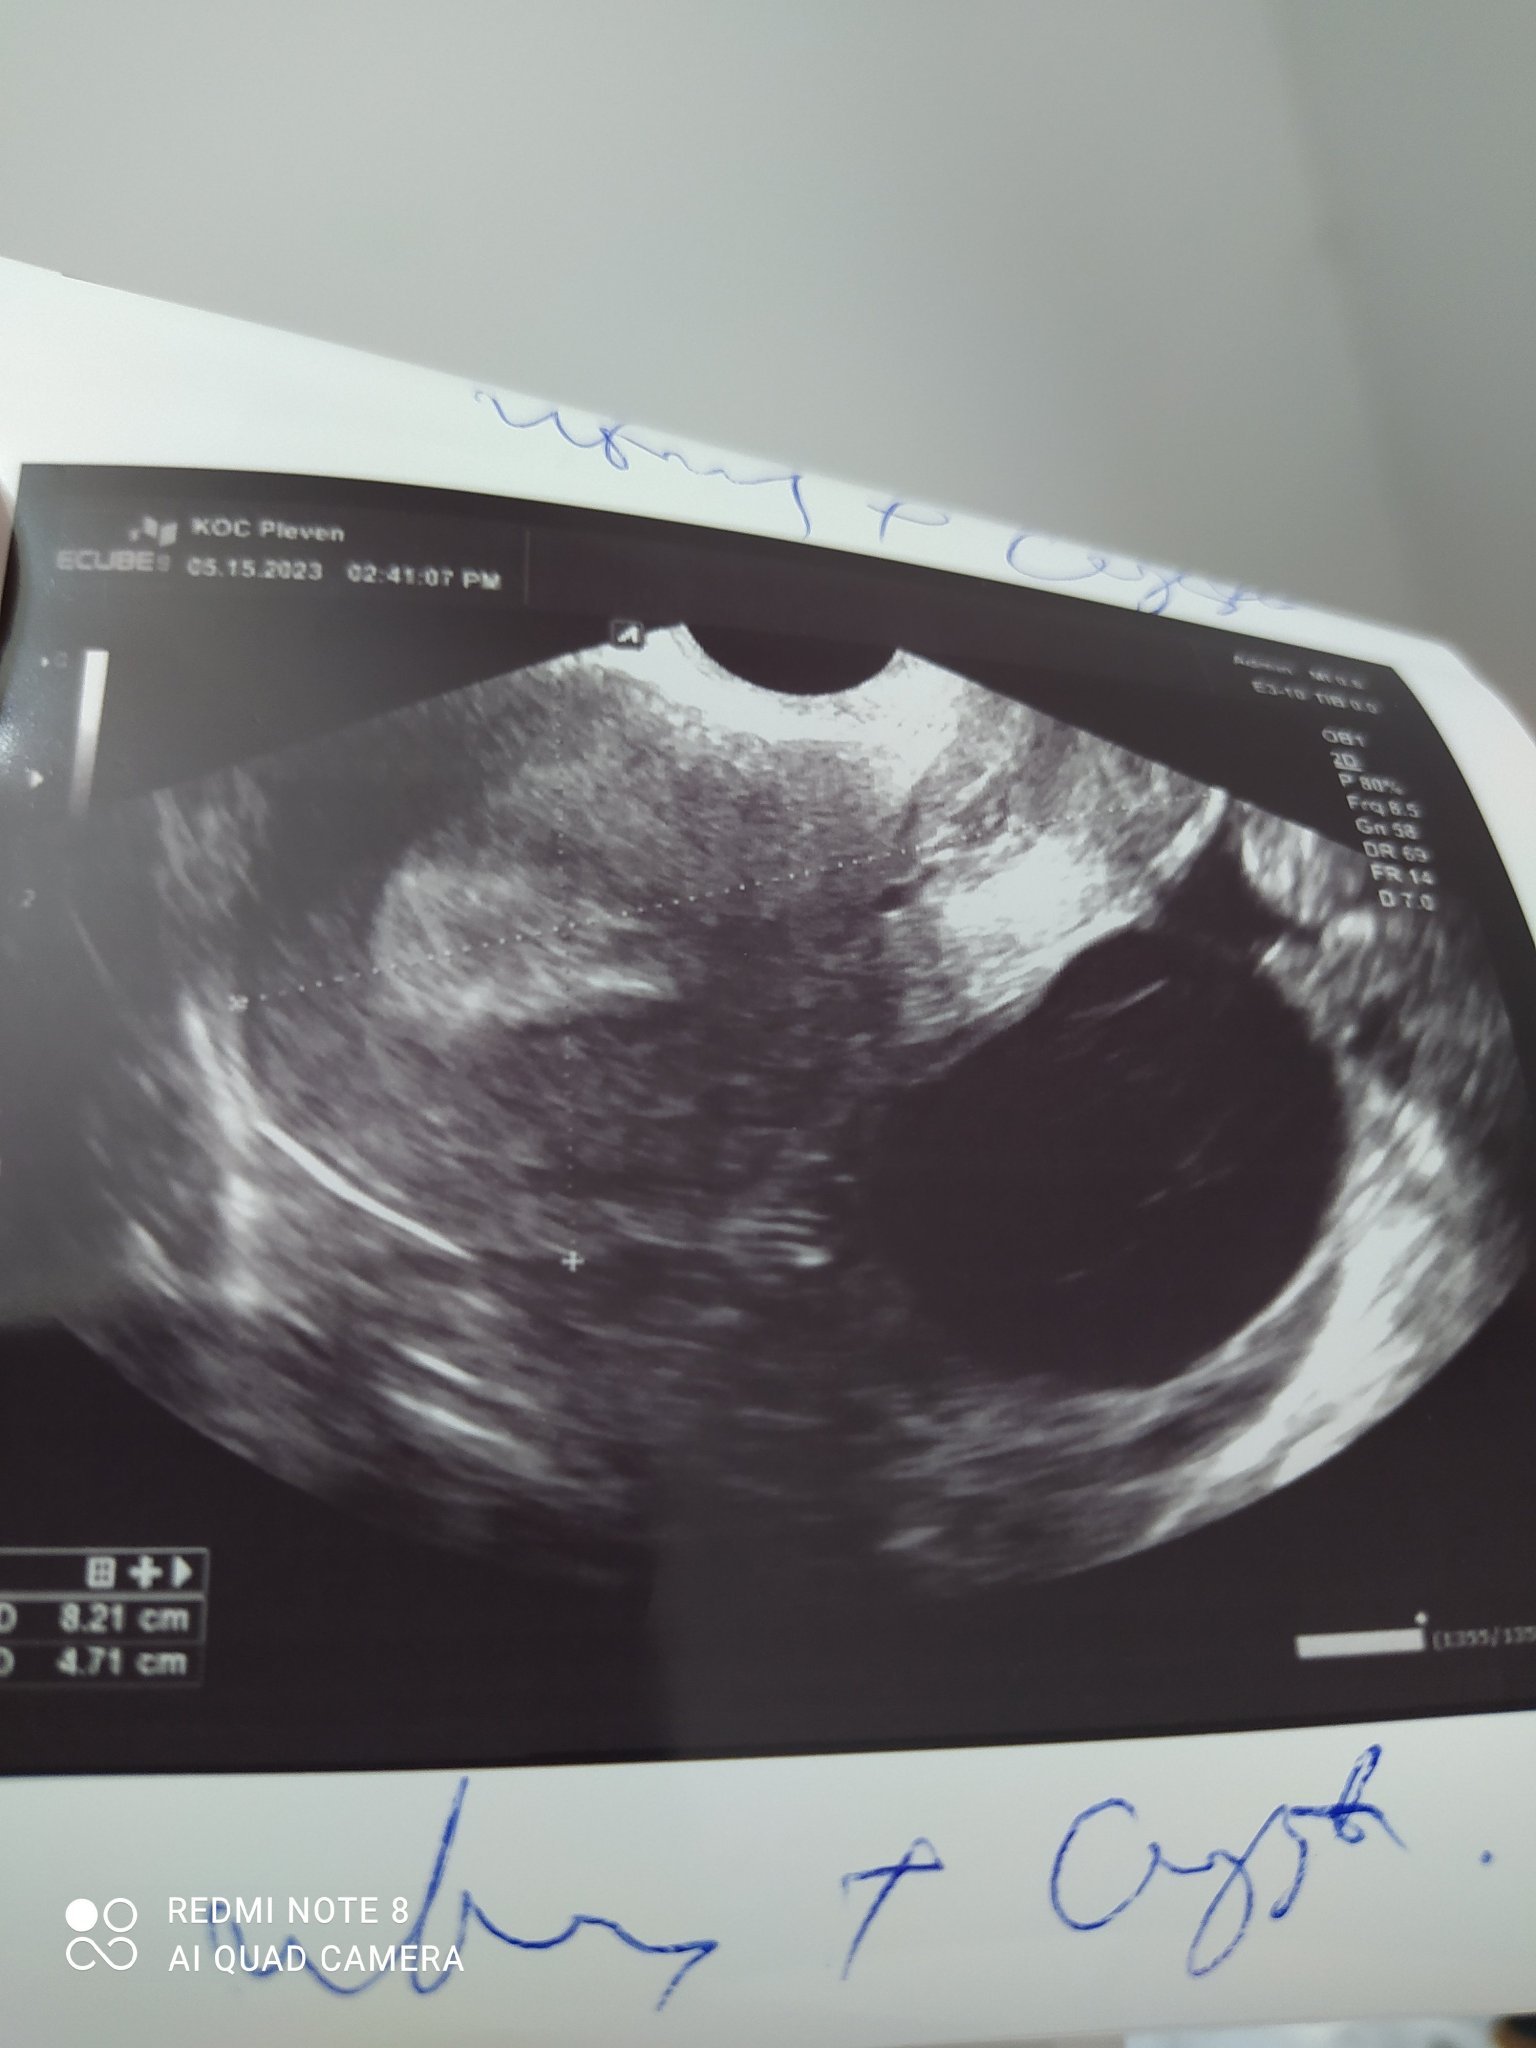

За да се определи дали киста на яйчника е злокачествена или доброкачествена, се извършват различни тестове. Тези тестове включват ултразвук, ЯМР и кръвни изследвания като CA-125, HE4, ROMA и други. Нормалните стойности на тези тестове обикновено показват липса на злокачествено заболяване; обаче окончателната диагноза се поставя от специалист след преглед на резултатите.